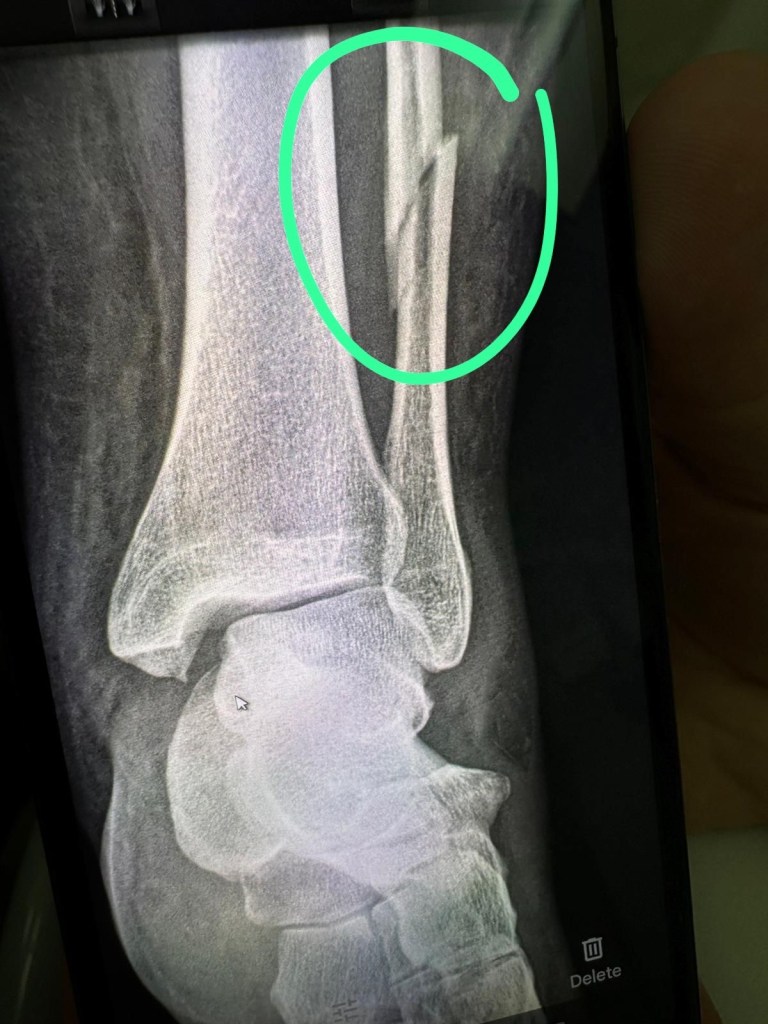

On June 8 of this year, my life took an unexpected turn when I broke my leg in a freak accident on an airplane, just as I was setting off on what was supposed to be an unforgettable month-long adventure through Spain and Morocco. Instead, I found myself stranded in Switzerland, navigating two surgeries, months of immobility, and the humbling challenge of learning to walk again. That injury wasn’t just a physical setback—it shook the foundations of my independence and identity. But through the pain and frustration, I found an unlikely lifeline in pottery, a practice that became my sanctuary, my therapy, and my connection to the community that carried me through.